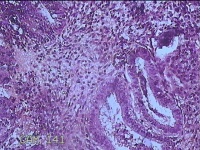

子宫腔赘生物

性别

女

年龄

33岁

临床诊断

子宫内膜息肉?子宫异常出血

一般病史

阴道流血12天。

标本名称

大体所见

灰白粉红色不规则肿物1.5x1.3x0.2cm一堆,表面糜烂。